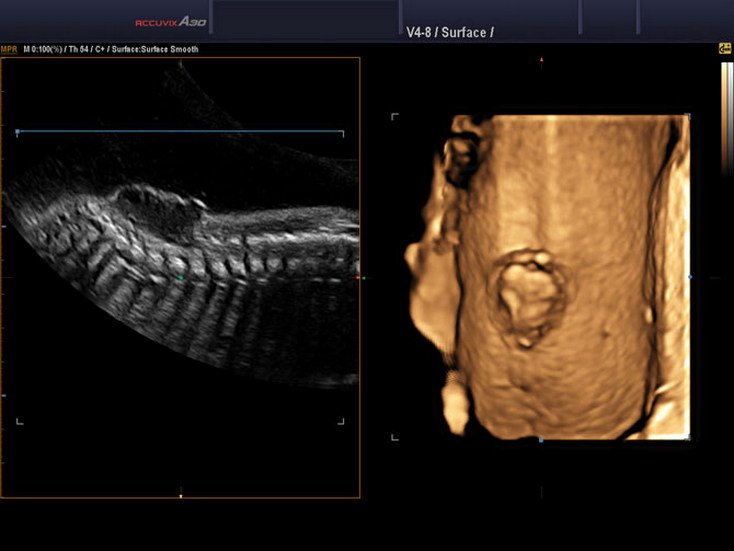

2D Sonography-Foetal Spine

Spinal Defect Sonography